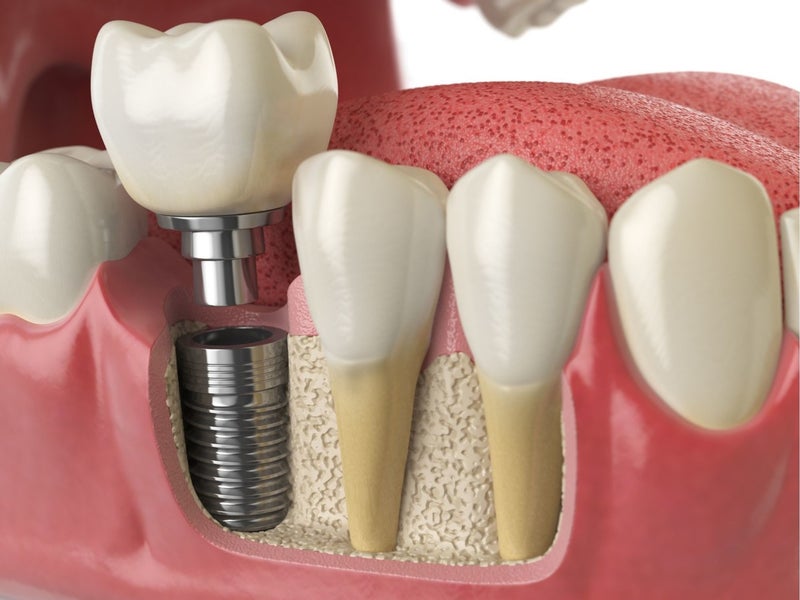

Nếu quyết định trồng lại răng, có nhiều phương pháp để lựa chọn, bao gồm cấy ghép implant, cầu răng hay hàm giả. Cấy ghép implant thường được coi là giải pháp tối ưu vì nó giúp phục hồi chức năng nhai và bảo tồn xương hàm, đồng thời mang lại vẻ đẹp tự nhiên cho nụ cười.

Tuy nhiên, trước khi quyết định trồng lại, bạn nên tham khảo ý kiến bác sĩ nha khoa để được tư vấn cụ thể về tình trạng của mình. Bác sĩ sẽ xem xét các yếu tố như độ tuổi, sức khỏe tổng quát và tình trạng xương hàm để đưa ra giải pháp phù hợp nhất. Việc trồng lại răng số 7 không chỉ giúp cải thiện chức năng nhai mà còn góp phần nâng cao chất lượng cuộc sống và tự tin trong giao tiếp.

Cấy ghép implant là một lựa chọn tốt cho việc trồng lại răng số 7